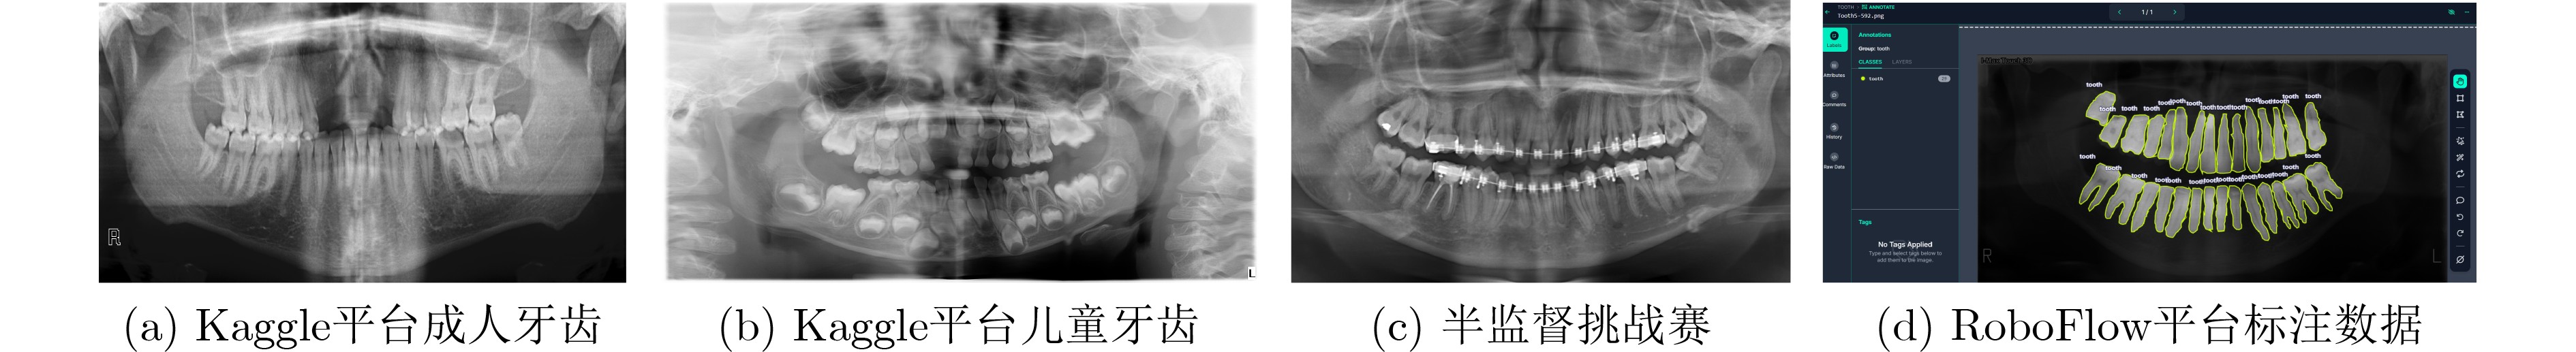

摘要: 针对口腔颌面全景X射线图像中存在的形态变异显著、牙体-牙龈边界模糊以及牙周组织灰度值重叠等问题,该研究提出基于双域多尺度状态空间网络的口腔颌面全景X射线图像分割算法。空间域利用视觉状态空间块建立牙弓动态传播模型,并利用微分方程实现跨象限长程关联捕捉。特征域构建可变形多尺度注意力金字塔,并利用通道-空间注意力动态加权关键解剖标志的灰度渐变特征,解析牙体-牙龈模糊边界。双域特征进一步通过三重注意力融合机制,强化解剖标注的语义表达。实验表明,该算法在颌面全景X射线图像分割任务中取得显著效果,戴斯系数(Dice)达93.8%,豪斯多夫距离(HD95)为18.73像素,充分验证了算法的有效性。

Abstract:Objective To address significant morphological variability, blurred boundaries between teeth and gingival tissues, and overlapping grayscale distributions in periodontal regions of oral and maxillofacial panoramic X-ray images, a state space model based on Mamba, a recently proposed neural network architecture, is adopted. The model preserves the advantage of Convolutional Neural Networks (CNNs) in local feature extraction while avoiding the high computational cost associated with Transformer-based methods. On this basis, a Dual-Domain Multiscale State Space Network (DMSS-Net)-based segmentation algorithm for oral and maxillofacial panoramic X-ray images is proposed, resulting in notable improvements in segmentation accuracy and computational efficiency. Methods An encoder–decoder architecture is adopted. The encoder consists of dual branches to capture global contextual information and local structural features, whereas the decoder progressively restores spatial resolution. Skip connections are used to transmit fused feature maps from the encoding path to the decoding path. During decoding, fused features gradually recover spatial resolution and reduce channel dimensionality through deconvolution combined with upsampling modules, finally producing a two-channel segmentation map. Results and Discussions Ablation experiments are conducted to validate the contribution of each module to overall performance, as shown in Table 1 . The proposed model demonstrates clear performance gains. The Dice score increases by 5.69 percentage points to 93.86%, and the 95th percentile Hausdorff distance (HD95) decreases by 2.97 mm to 18.73 mm, with an overall accuracy of 94.57%. In terms of efficiency, the model size is 81.23 MB with 90.1 million parameters, which is substantially smaller than that of the baseline model, enabling simultaneous improvement in segmentation accuracy and reduction in parameter count. Comparative experiments with seven representative medical image segmentation models under identical conditions, as reported inTable 2 , show that the DMSS-Net achieves superior segmentation accuracy while maintaining a model size comparable to, or smaller than, Transformer-based models of similar scale.Conclusions A DMSS-Net-based segmentation algorithm for oral and maxillofacial panoramic X-ray images is proposed. The algorithm is built on a dual-domain fusion framework that strengthens long-range dependency modeling in dental images and improves segmentation performance in regions with indistinct boundaries. The spatial-domain design effectively supports long-range contextual representation under dynamically varying dental arch morphology. Moreover, enhancement in the feature domain improves sensitivity to low-contrast structures and increases robustness against image interference. -